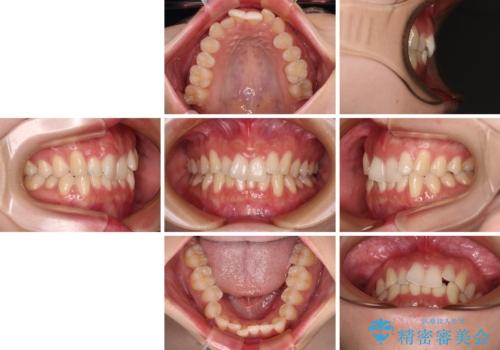

- 前歯のデコボコを気にして来院された患者様です。

全体的にデコボコが多く、特に下の前歯は隠れてしまうほどの状態でした。

左右ともに奥歯の咬み合わせが理想的な位置にあったこともあり、患者様のご希望通り、インビザラインにて矯正治療を行うこととしました。

マウスピース矯正特有の、奥歯が噛みにくくなるという現象の解消に少し期間をいただきましたが、日々の装着時間を遵守していただき、綺麗な歯列に整えることができました。